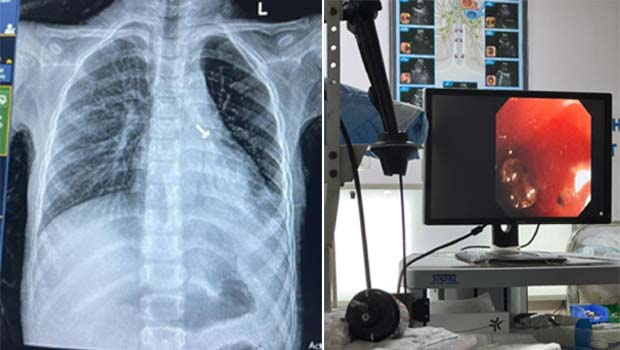

ऋषिकेश। अखिल भारतीय आयुर्विज्ञान संस्थान (Aiims) के पल्मोनरी मेडिसिन विभाग के चिकित्सकों ने ब्रोंकोस्कोपी प्रयोगशाला में एक 07 वर्षीय बच्चे के फेफड़े में फंसे पेंच को निकालकर उसे जीवनदान दिया है। बच्चा अब पूरी तरह से स्वस्थ है।

पल्मोनरी मेडिसिन विभाग की आचार्य डॉ. रुचि दुआ ने जानकारी दी कि बालरोग विभाग के चिकित्सक डॉ. व्यास कुमार राठौड़ के अनुसार भरत नगर, रुड़की निवासी एक 07 वर्ष के बच्चे को उसके परिजनों द्वारा 15 दिनों से उल्टी और खांसी की शिकायत के चलते ओपीडी में लाया गया था। प्रारंभिक जांचों एक्स-रे व सीटी स्कैन में बच्चे के फेफड़े में एक पेंच दिखाई दिया है। परिजनों ने बताया कि बच्चे ने खेल-खेल में पेंच निगल लिया, जिसका पता परिजनों को नहीं लग पाया।

डॉ. रुचि दुआ और टीम सदस्य डॉ. प्रखर शर्मा, डॉ. दीपांश गुप्ता, डॉ. ऋत्विक सिंगला, डॉ. अश्वथी साबू, डॉ. व्यास कुमार राठौड़, डॉ. मान सिंह, डॉ. श्रीजन, एनेस्थीसिया विशेषज्ञ डॉ. प्रियंका गुप्ता, डॉ. रीना, डॉ. अजहर, बाल शल्य चिकित्सा विशेषज्ञ डॉ. शौर्या, रेडियोलॉजिस्ट डॉ. राहुल देव की देखरेख में ब्रोंकोस्कोपी प्रयोगशाला में Flexible Bronchoscopy से बच्चे के फेफड़े से पेंच को निकाला गया।